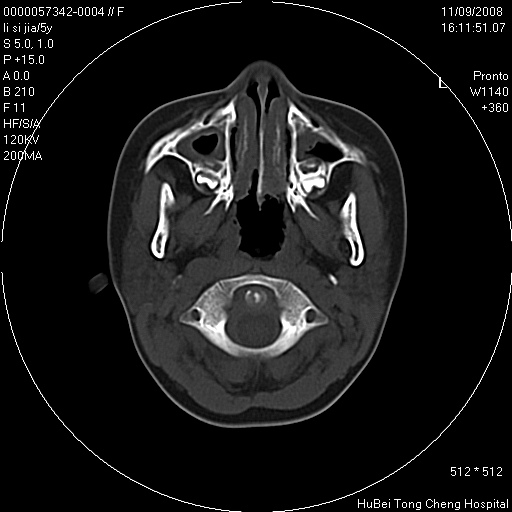

患儿 女,5岁。鼻塞、流涕2年余。

临床诊断:慢性副鼻窦炎?

副鼻窦ct轴位平扫(层厚、层距均为5mm),图像如下:

1、上颌窦、筛窦、蝶窦炎。2、腺样体肥大